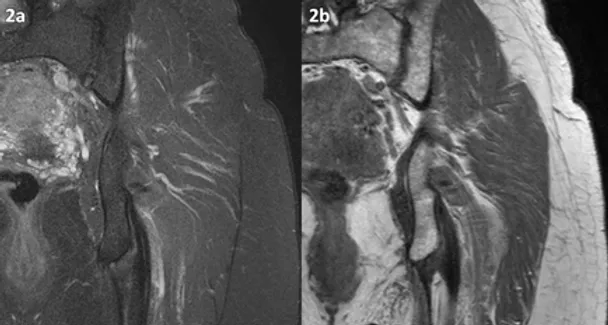

Figura 2 (a-b): Imagens do quadril esquerdo no plano coronal nas ponderações T2 com supressão de gordura (2a) e T1 (2b).

Figura 2 (a-b)’: Imagens do quadril esquerdo no plano coronal nas ponderações T2 com supressão de gordura (2a) e T1 (2b) mostrando a tendinopatia com rotura de grande parte das fibras na origem dos tendões bíceps femoral e semitendinoso (setas amarelas) e a tendinopatia com lesão parcial do tendão semimembranoso (setas azuis).